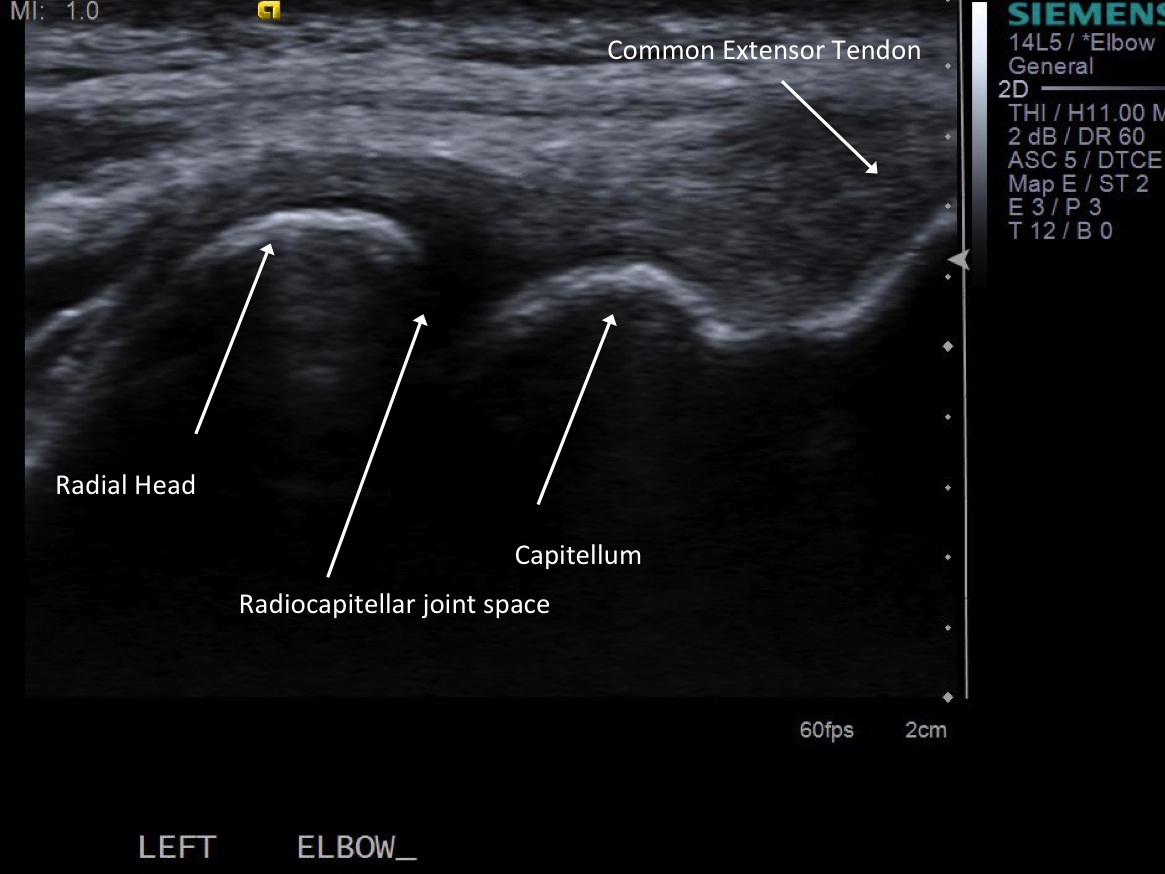

Picture of probe overlying the radiocapitellar joint. |

| 3. Place probe perpendicular to the joint and mark probe location and probable injection site |